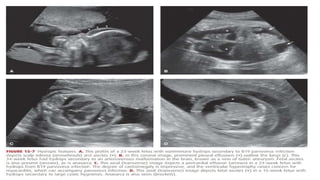

• Figure 15.6

• Figure 15.7

• #22 Diagnostic Evaluation Hydrops is readily detected sonographically. As noted, two effusions or one effusion plus anasarca are required for diagnosis. Edema may be particularly prominent around the scalp, or equally obvious around the trunk and extremities. Effusions are visible as fluid outlining the lungs, heart, or abdominal viscera (Fig. 15-7). In many cases, targeted sonographic and laboratory evaluation will identify the underlying cause of fetal hydrops. These include cases due to fetal anemia, arrhythmia, structural abnormality, aneuploidy, placental abnormality, or complications of monochorionic twinning. Depending on the circumstances, initial evaluation includes the following: 1. Indirect Coombs test for alloimmunization 2. Targeted sonographic fetal and placental examination, including: • A detailed anatomic survey to assess for the structural abnormalities listed in Table 15-4 • MCA Doppler velocimetry to assess for fetal anemia • Fetal echocardiography with M-mode evaluation 3. Amniocentesis for fetal karyotype and for B19 parvovirus, cytomegalovirus, and toxoplasmosis testing as discussed in Chapter 64. Consideration of chromosomal microarray analysis if fetal anomalies are present 4. Consideration of Kleihauer-Betke test for fetomaternal hemorrhage if anemia is suspected, depending on findings and test results 5. Consideration of testing for α-thalassemia and/or inborn errors of metabolism